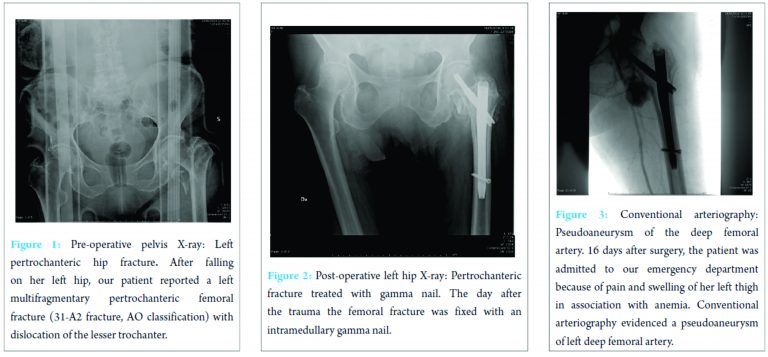

A 90-year-old female was admitted to our emergency department after falling on her left hip. On physical examination, the patient’s left leg was painful, shorter, and in external rotation. The patient was completely unable to bear any weight on it. A radiograph of her hips and pelvis showed a left multifragmentary pertrochanteric femoral fracture (31-A2 fracture, AO Classification) with dislocation of the lesser trochanter (Fig. 1).

The day after, the fracture was fixed by means of an intramedullary nail without perioperative complications (Fig. 2). The post-operative course was regular apart from mild post-surgical anemia on the second post-operative day that was treated with two blood transfusions. On the 5th post-operative day, general conditions of the patient were good and the surgical wound had no signs of infection and no exudate, so she was discharged. 16 days after discharge, the patient made a new access to our emergency department for the appearance of severe anemia, pain, and swelling of her left hip. First of all, Doppler ultrasound was performed, and a large pseudoaneurysm of the proximal part of the profunda femoris artery was found. Her hemoglobin value was 7.7 g/dL, so she was urgently transfused. Then, left lower extremity arteriogram was performed and confirmed the diagnosis (Fig. 3).

Therefore, a stent was placed (Fig. 4). After this procedure, the clinical conditions improved and the patient was discharged 4 days later with stable blood exams. On the last clinical control, 3 months after the stenting, the patient was feeling well and had started physical rehabilitation.